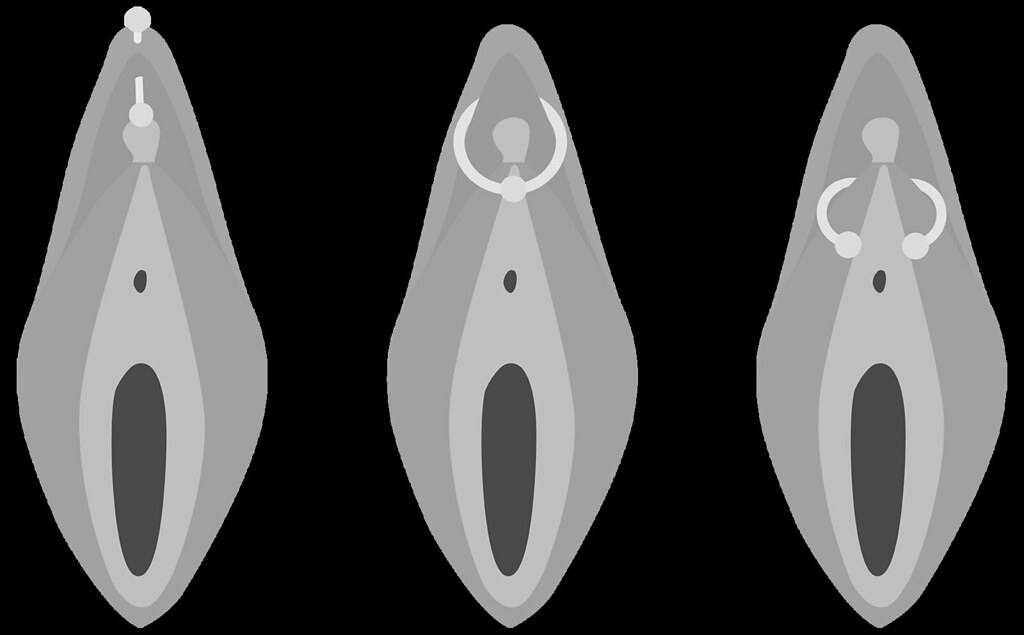

To understand why this piercing is so profoundly dangerous, you must understand the path it takes through some of the most sensitive and functionally critical anatomy of the human body.

The Definition: A Deep, High-Risk Vertical Channel

The Isabella is a deep, vertical piercing. On the surface, it appears as two beads: one sitting just below where a Christina piercing would be (on the pubic mound) and the other emerging just above the urethral opening. The channel connecting these two points, however, is what makes it so perilous. The jewellery—a long, straight or curved barbell—is forced to travel:

- Deeply underneath the clitoral hood.

- Directly through or underneath the clitoral shaft and the bundle of nerves it contains.

- Through the highly vascular corpus spongiosum tissue.

- In extremely close proximity to the urethra.

This is not a surface piercing. It is a deep, invasive procedure that traverses a landscape of vital neurological and sexual structures.